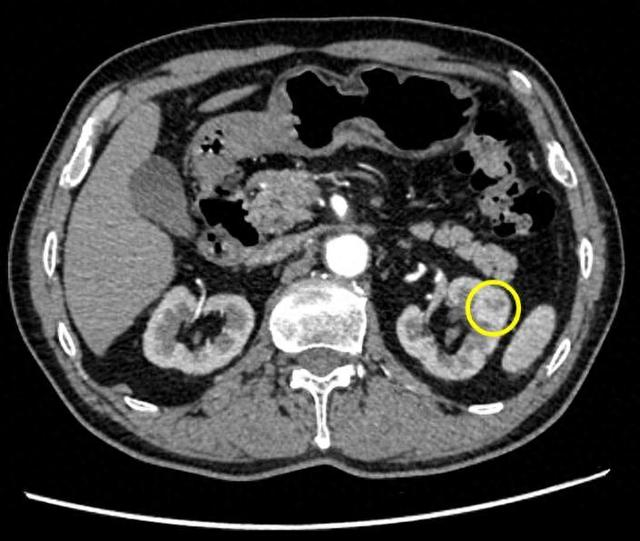

72岁的陈老伯在一次体检中发现在其胃窦体交界处有一处周围隆起、中央凹陷性的病灶,活检病理提示倾向认为是低分化腺癌。陈老伯随后来到仁济医院胃肠外科表示希望进行根治性手术治疗。但在入院检查中,医院意外发现陈老伯的右肾中部有个1公分结节,增强CT高度怀疑肾癌。